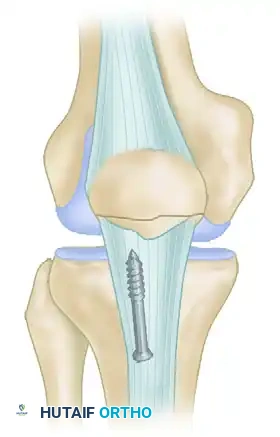

- Internal Fixation: The fracture is reduced and secured using parallel, vertical 4.0 mm partially threaded cancellous screws inserted from distal to proximal through the inferior pole.

- Suture Augmentation: If the bone quality is poor or the fragment is highly comminuted, the fixation can be augmented with heavy nonabsorbable sutures (e.g., No. 5 FiberWire) passed circumferentially through the screw holes or around the screw heads in a tension-band configuration.

- Corticocancellous Slot Graft (Optional but Recommended): To enhance biological healing and provide structural support, an oscillating saw is used to harvest a corticocancellous slot graft (typically 10 mm wide × 15 mm long) from the anterior surface of the proximal patella. This graft is then translated distally across the fracture site.

FIGURE 48-28: Stress fracture of the inferior pole of the patella in a collegiate basketball player. The fracture is secured with parallel screws, and a corticocancellous slot graft is placed distally across the fracture site to promote osteosynthesis.